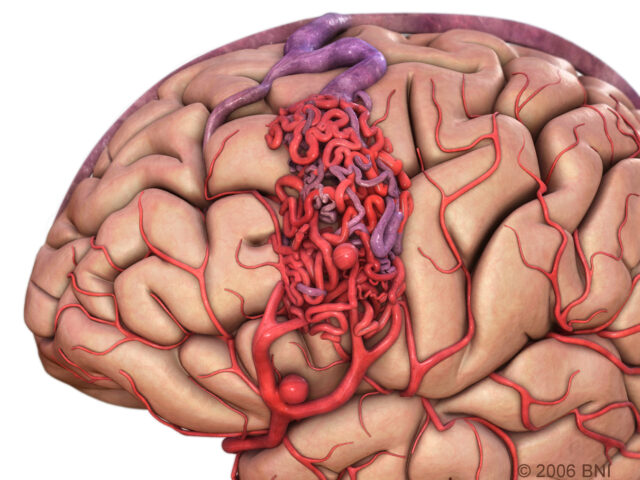

Снимки и иллюстрации микроаневризм сосудов головного мозга